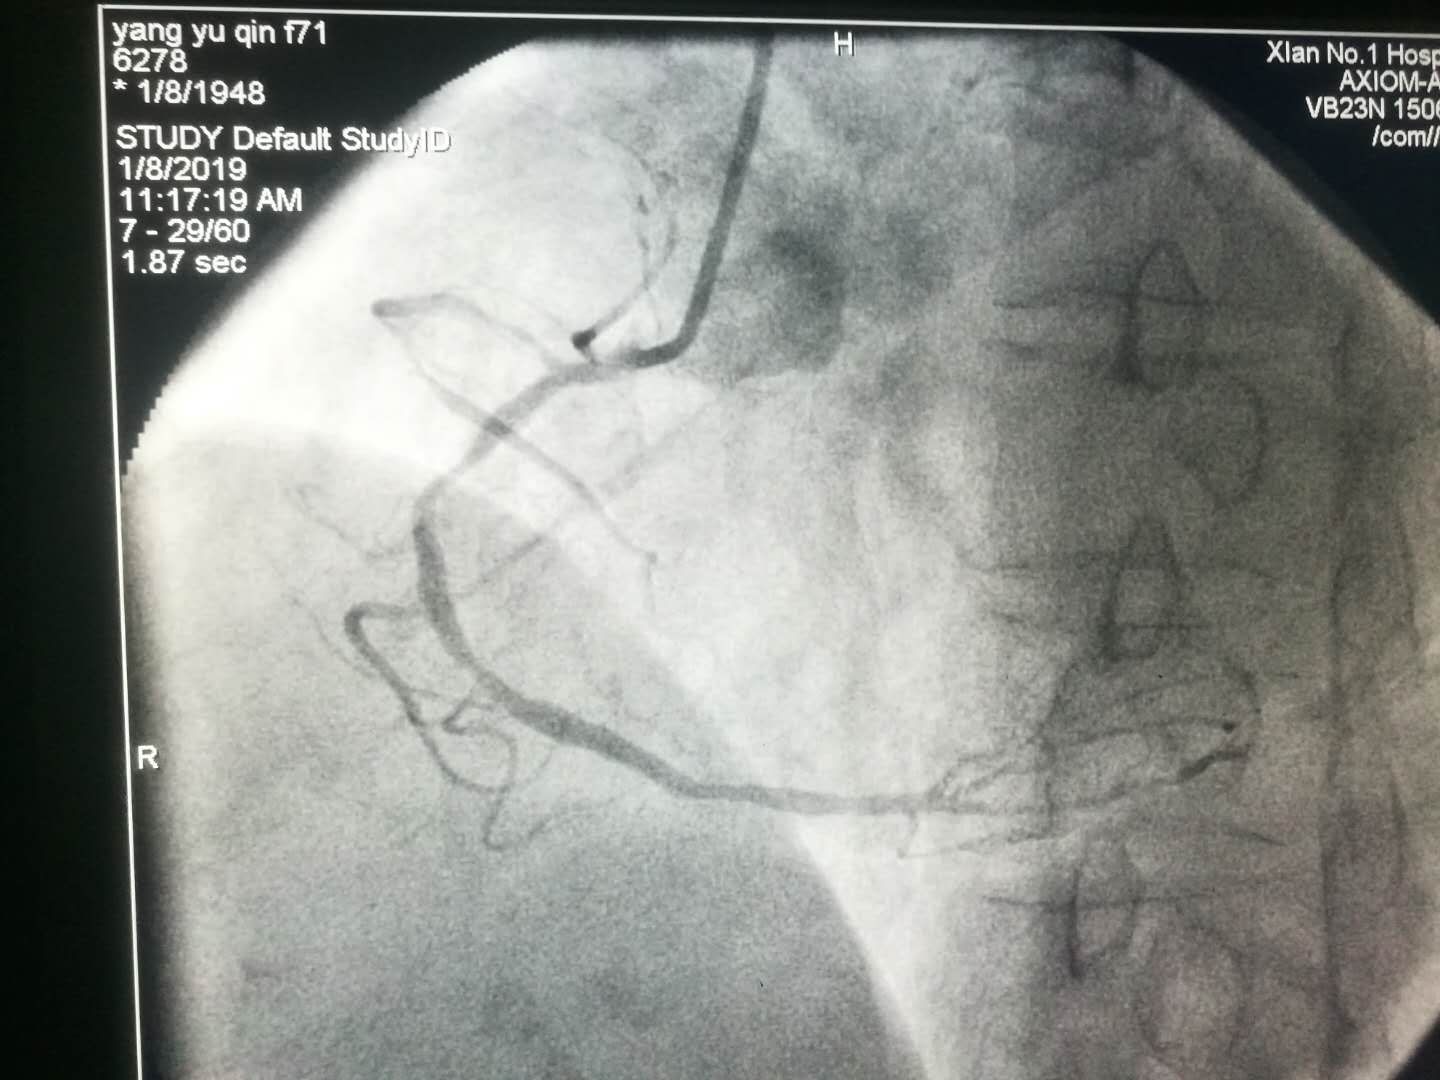

2019新年伊始,文理病区开展了首例冠状动脉造影术及冠状动脉支架植入术。

1月8日上午患者术后在李同华主任的协助下完成文理病区首例冠状动脉造影术加冠状动脉支架植入术。术后患者转入心内四病区监护48小时,1月9日患者平安转回我科继续治疗。整个转诊过程无缝衔接,配合顺畅心血管病成人导航 的各位主任护士长们纷纷表示,只要文理病区需要,术后患者可以转往心血管成人导航 任何一个病区监护。距离无法阻隔我们发展的脚步,无法阻隔我们团结一致为患者服务的信心。